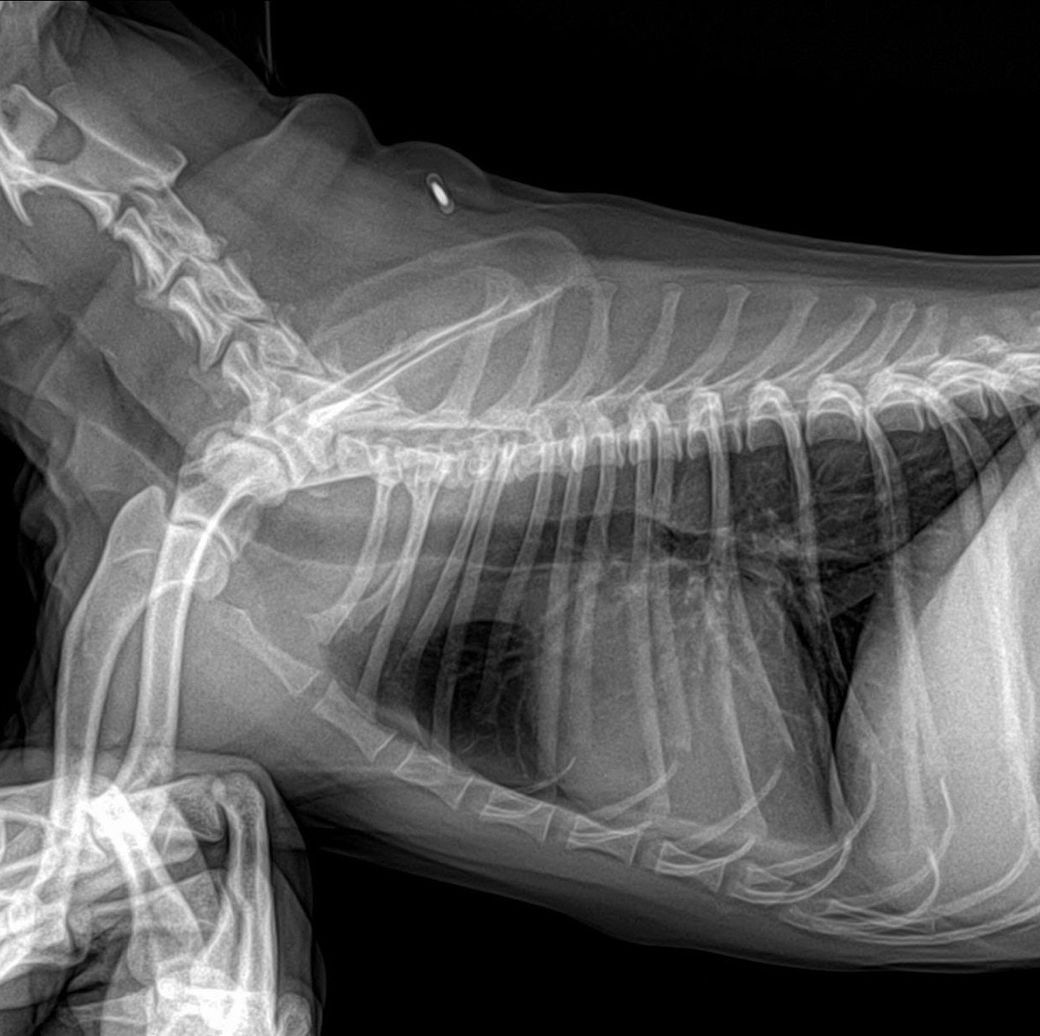

기관지 협착도 걱정되어서 엑스레이 사진도 같이 첨부해요!

기관지 협착은 아니겠죠..?

심장의 크기는 정상적이지만 심장의 흉골 접합 면적 증가 양상이 관찰되어 우심계 문제 가능성을 고려해야 합니다. 심장 초음파 검사가 가능한 동물병원에 데려가서 심장 초음파 검사를 받아 보시기 바랍니다.